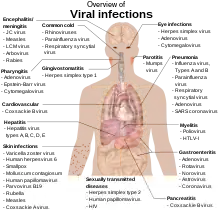

Virus y enfermedades humanas

Ejemplos de enfermedades humanas comunes provocadas por virus son el resfriado, la gripe, la varicela y el herpes simple.[173][174][175] Muchas enfermedades graves como el ébola, el sida, la gripe aviar y el SARS son causadas por virus.[176][177][178] La capacidad relativa de los virus de provocar enfermedades se describe en términos de «virulencia». Otras enfermedades están siendo investigadas para descubrir si su agente causante también es un virus, como la posible conexión entre el herpesvirus humano 6 (HHV6) y enfermedades neurológicas como la esclerosis múltiple y el síndrome de fatiga crónica.[179] Actualmente existe un debate sobre si el bornaviridae, antiguamente considerado la causa de enfermedades neurológicas en los caballos, podría ser la causa de enfermedades psiquiátricas en los humanos.[180]

Los virus tienen diferentes mecanismos mediante los cuales causan enfermedades a un organismo, que dependen en gran medida de la especie de virus. Los mecanismos a nivel celular son principalmente la lisis de la célula, es decir, la ruptura y posterior muerte de la célula. En los organismos pluricelulares, si mueren demasiadas células del organismo en general comenzará a sufrir sus efectos. Aunque los virus causan una disrupción de la homeostasis saludable, provocando una enfermedad, también pueden existir de manera relativamente inofensiva en un organismo. Un ejemplo sería la capacidad del virus del herpes simple de permanecer en un estado durmiente dentro del cuerpo humano. Esto recibe el nombre de «latencia»[181] y es una característica de todos los herpesvirus, incluyendo el virus de Epstein-Barr (que causa mononucleosis infecciosa) y el virus de la varicela zóster (que causa la varicela). Las infecciones latentes de varicela pueden generarse posteriormente en la etapa adulta del ser humano en forma de la enfermedad llamada herpes zóster.[182] Sin embargo, estos virus latentes algunas veces suelen ser beneficiosos, incrementando la inmunidad del cuerpo contra algunos seres patógenos, como es el caso del Yersinia pestis.[183] Cuando alguna enfermedad viral vuelve a aparecer en cualquier etapa de la vida se conoce popularmente como culebrilla.

Algunos virus pueden causar infecciones permanentes o crónicas, en las que los virus continúan replicándose en el cuerpo a pesar de los mecanismos de defensa del huésped.[184] Esto es habitual en las infecciones de virus de la hepatitis B y de la hepatitis C. Los enfermos crónicos son conocidos como portadores, pues sirven de reservorio de los virus infecciosos.[185] En poblaciones con una proporción elevada de portadores, se dice que la enfermedad es endémica.[186] Algunos virus pueden mutar dentro de las células huéspedes, reforzando sus defensas contra diversos antivirales, proceso conocido como mutación.[187]